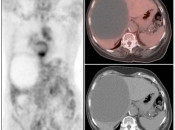

The normal liver demonstrates diffuse FDG uptake (typically greater than or equal to the spleen).

Many readers consider the uptake in the liver to represent the “background metabolic activity” for an exam.

For assessment of many lesions found in the body, the metabolic activity of the liver serves as the reference threshold by which to decide what is benign (uptake < liver) and what is malignant (uptake > liver).

Focal increased FDG uptake in the liver is always highly suspicious for malignancy. Very commonly, these malignant lesions may be poorly delineated on the co-registered CT images due to the lack of intravenous contrast administration.

Non-avid, low attenuation liver lesions are almost always benign (usually representing cysts, hemangiomas or fully treated malignant lesions), although some hepatocellular carcinomas can demonstrate only very mild metabolic activity.